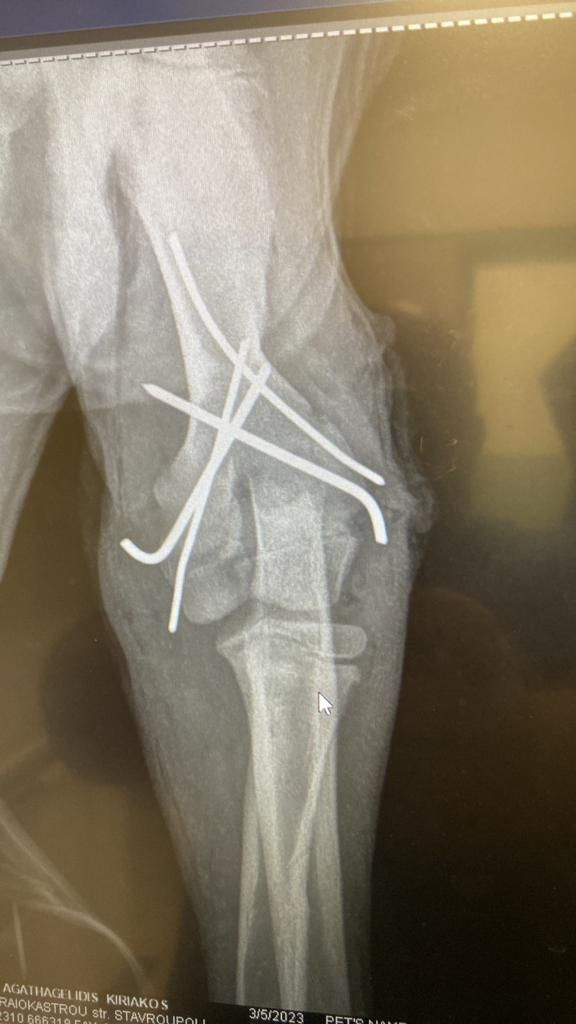

Aliki hat einen neuen Rüden in Obhut genommen. Dieser Hund, genannt Paok, ist ein Streuner, der in der Nähe ihrer Freundin Mareike lebte. Dort sind viele Häuser, viele Menschen, die ihn auch gefüttert haben. Eines Tages ist er aufgefunden worden, mit mehreren Knochenbrüchen. Die Gemeinde hat ihn aufgenommen und die Brüche operieren lassen.

Dann aber wurde er mal wieder sich selbst überlassen, und natürlich hat der Hund Schmerzen, so dass er den Gips aufgebissen hat. Aliki hat Mitleid mit dem armen Kerl und ihn erst mal aufgenommen. Sie wird versuchen, den Heilprozess in die richtige Richtung zu lenken, daher die Halskrause, die ein erneutes Aufbeißen verhindert. Aliki wird die Wunde täglich reinigen und so entzündungsfrei zu halten versuchen und Paok versorgen, bis er wieder zurück kann zu den Menschen, die ihn vorher bereits gefüttert haben. Anschließend wird sie sich darum kümmern, dass der Hund nun von der Straße ferngehalten wird. Aber erst heißt es einmal, dem armen Kerl die Daumen drücken und Aliki unterstützen, damit sie solche Hilfe Leistungen auch geben kann. 💙🥰